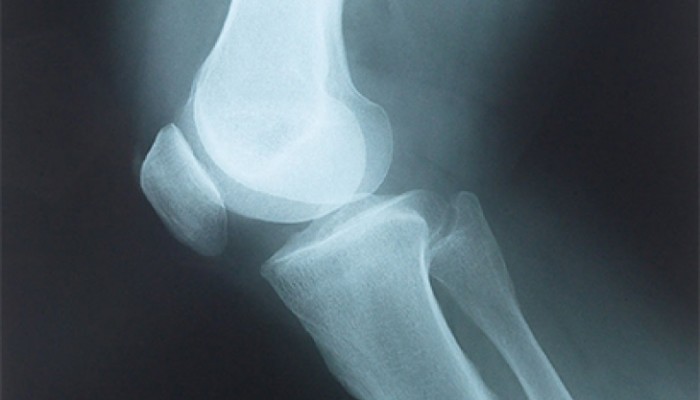

Прежде чем начинать лечение ушиба колена, врач должен убедиться, что внутренние структуры сустава не повреждены. Для этого могут быть назначены следующие исследования:

- Рентгенография коленных суставов – исключает переломы костей, образующих сочленение.